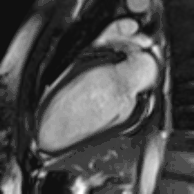

Enlarged right ventricle with poor function in a patient with repaired tetralogy of Fallot by CMR

Rather, it is typically used in concert with other diagnostic techniques. In general, the clinical reasons for a CMR examination fall into one or more of the following categories: (1) when echocardiography (cardiac ultrasound) cannot provide sufficient diagnostic information, (2) as an alternative to diagnostic cardiac catheterization which involve risks including x-ray radiation exposure, (3) to obtain diagnostic information for which CMR offers unique advantages such as blood flow measurement or identification of cardiac masses, and (4) when clinical assessment and other diagnostic tests are inconsistent. Examples of conditions in which CMR is often used include tetralogy of Fallot, transposition of the great arteries, coarctation of the aorta, single ventricle heart disease, abnormalities of the pulmonary veins, atrial septal defect, connective tissue diseases such as Marfan syndrome, vascular rings, abnormal origins of the coronary arteries, and cardiac tumors.